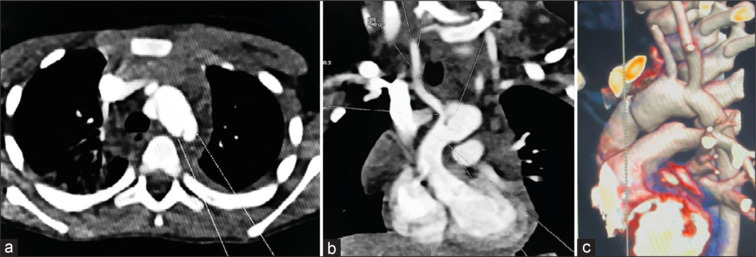

We present a case of a 4-year-old boy with posttraumatic non-A non-B aortic dissection. Pediatric aortic dissection is a rare entity with ill-defined risk factors. A high index of suspicion is needed to identify these patients with aggressive management to offset a high mortality rate. Diagnosis was established with a computed tomography scan, which showed a dissection flap in the aortic arch. The child was taken up for surgery and underwent successful aortic arch replacement with arch vessel reimplantation. We report this case not only because of its incidental rarity but also to highlight the meticulous planning and execution that was essential for a successful outcome.